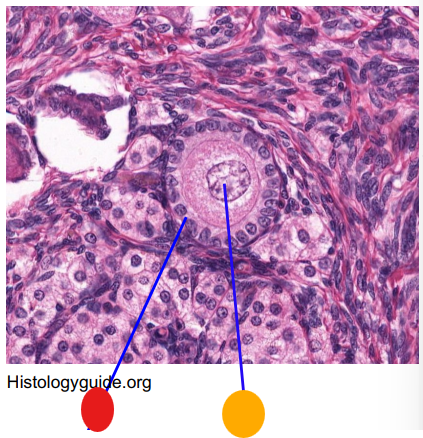

what is this

secondary follicle

what is this

tertiary follicle

what is this

tertiary follicle

What is this

mature follicle

red

cumulus oophorus

orange

tertiary follicle

yellow

intermediate tertiary to mature follicle